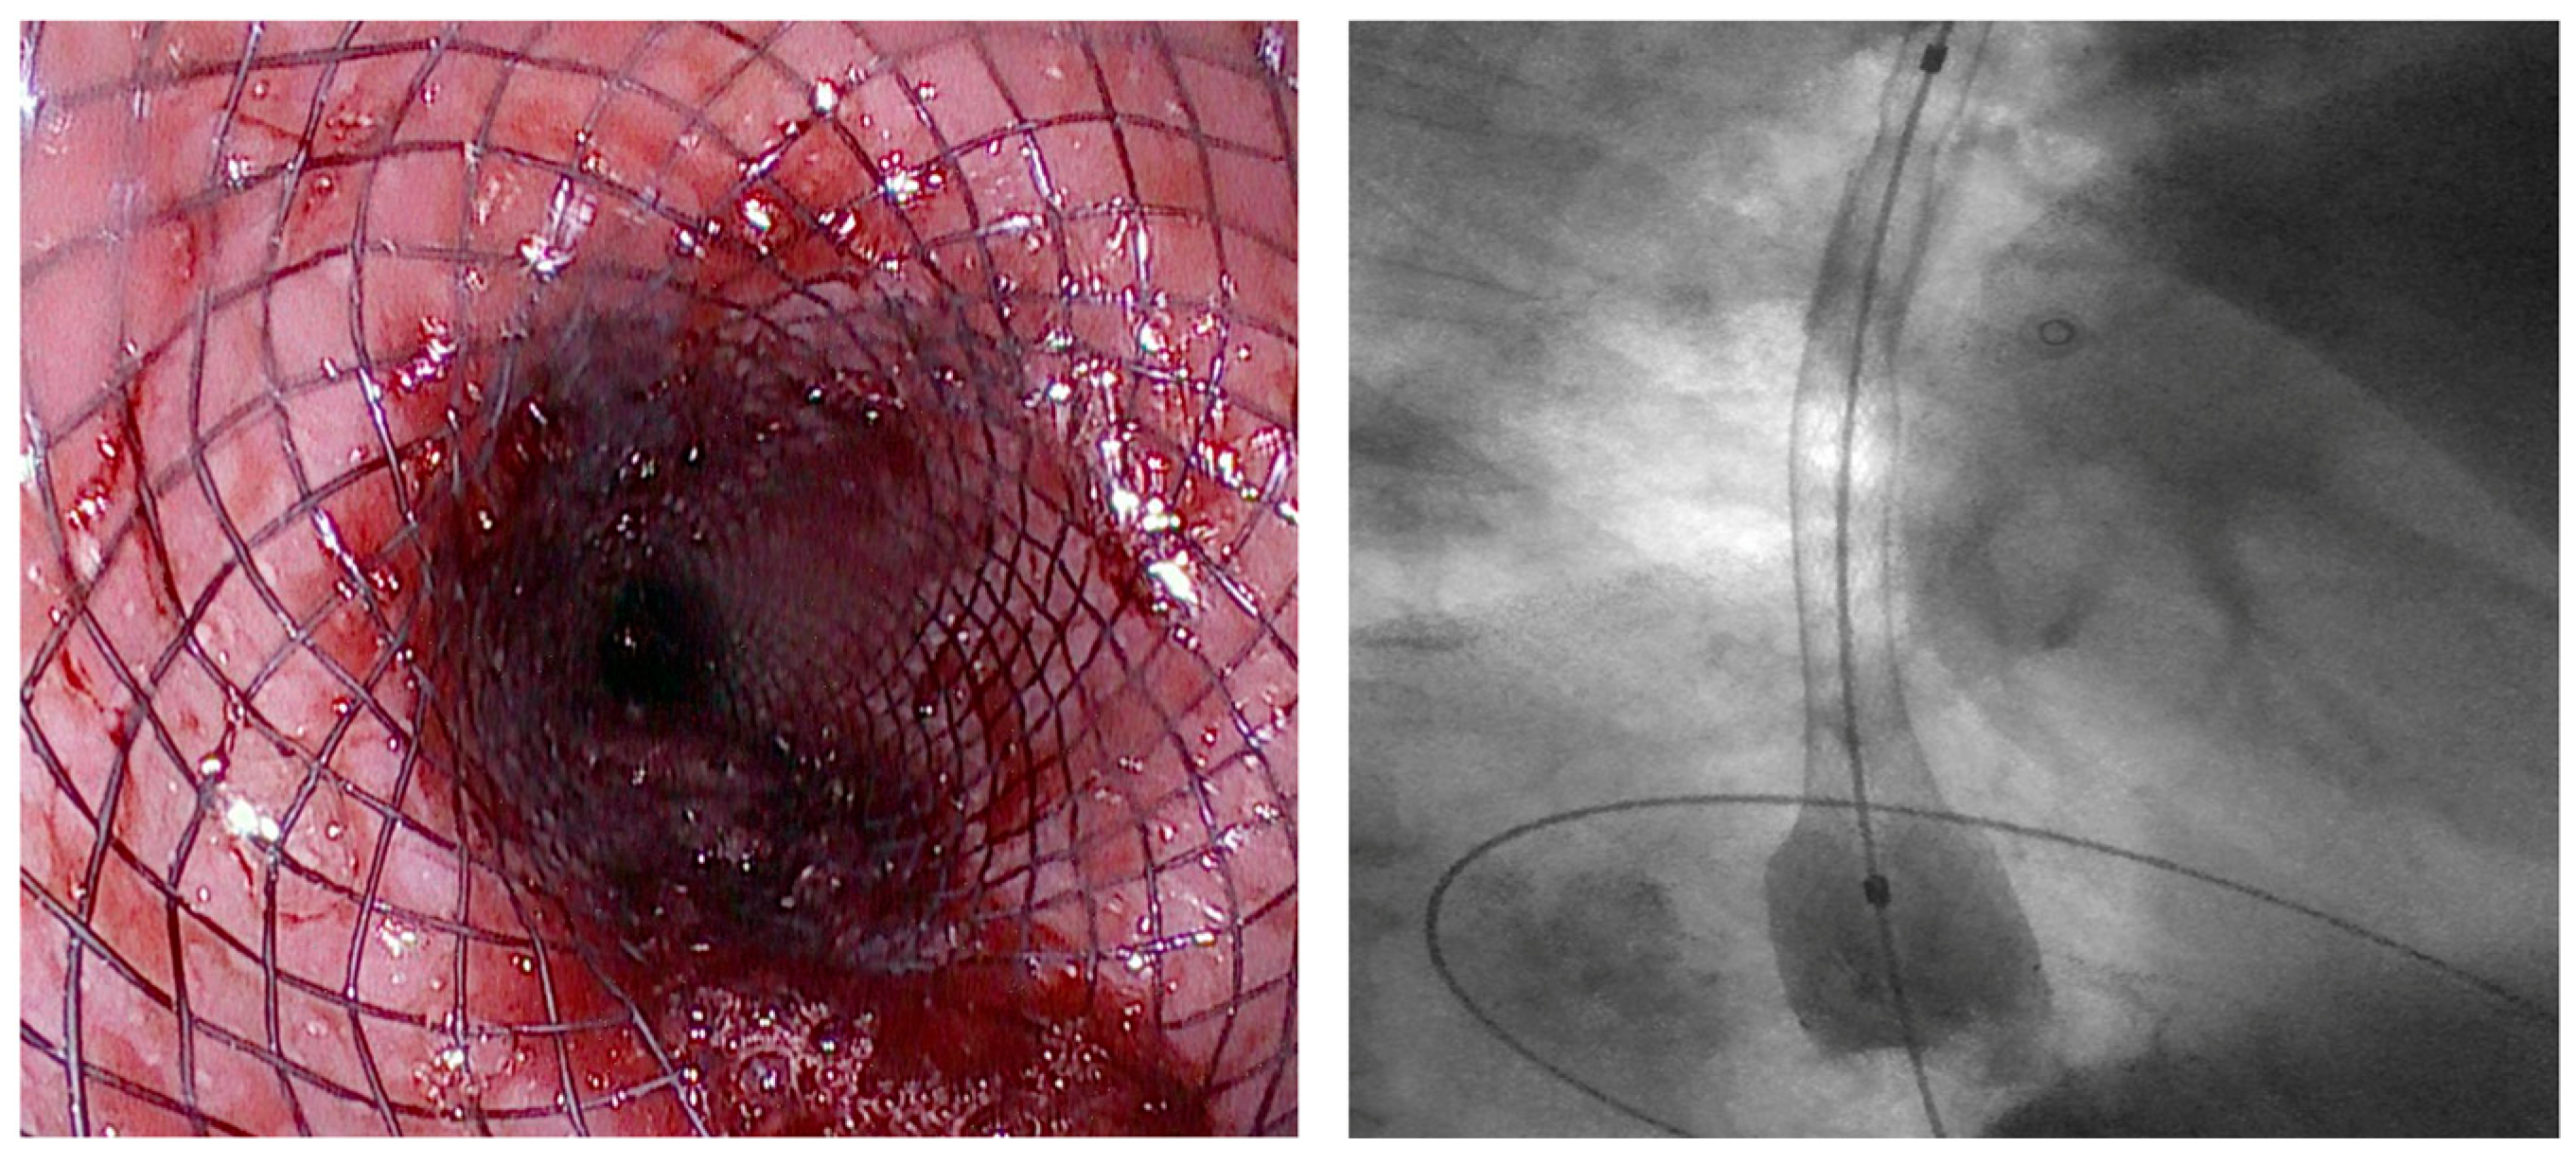

3.4. Esophageal Acute Variceal Bleeding

3.4.1. Role of Stent

Indication and Mechanism of Action

Efficacy and Adverse Events